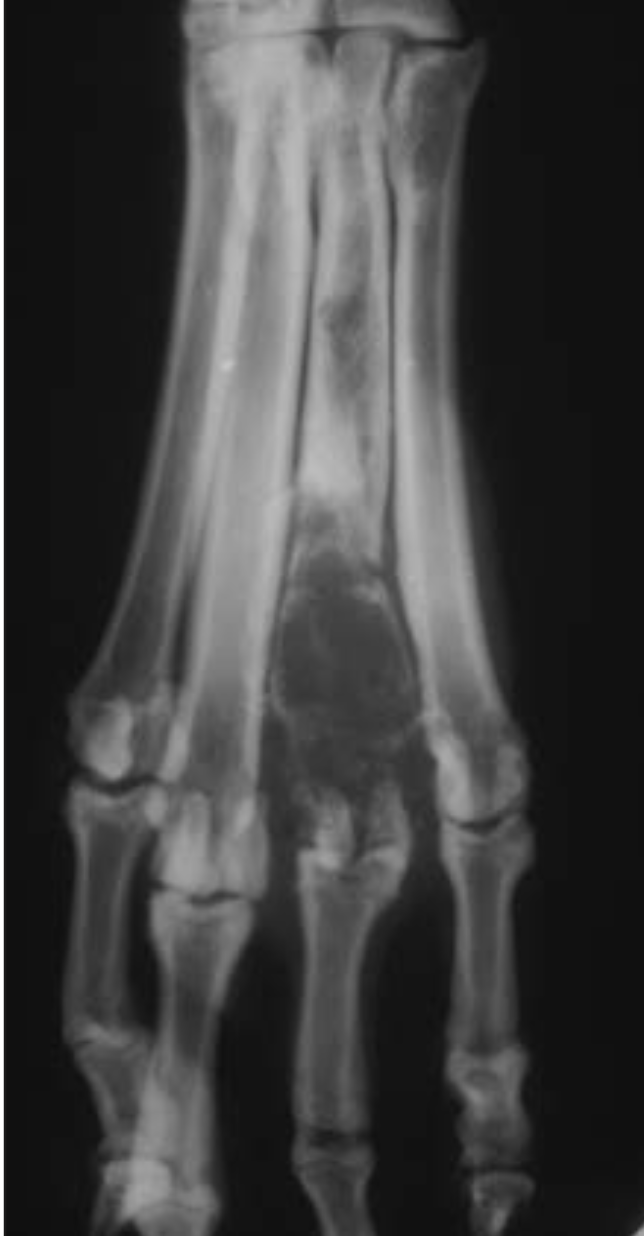

Q

A

Thin brush-like

periosteal reaction of the abaxial

surface of metatarsals II andVinacaseof hypertrophic osteopathy.